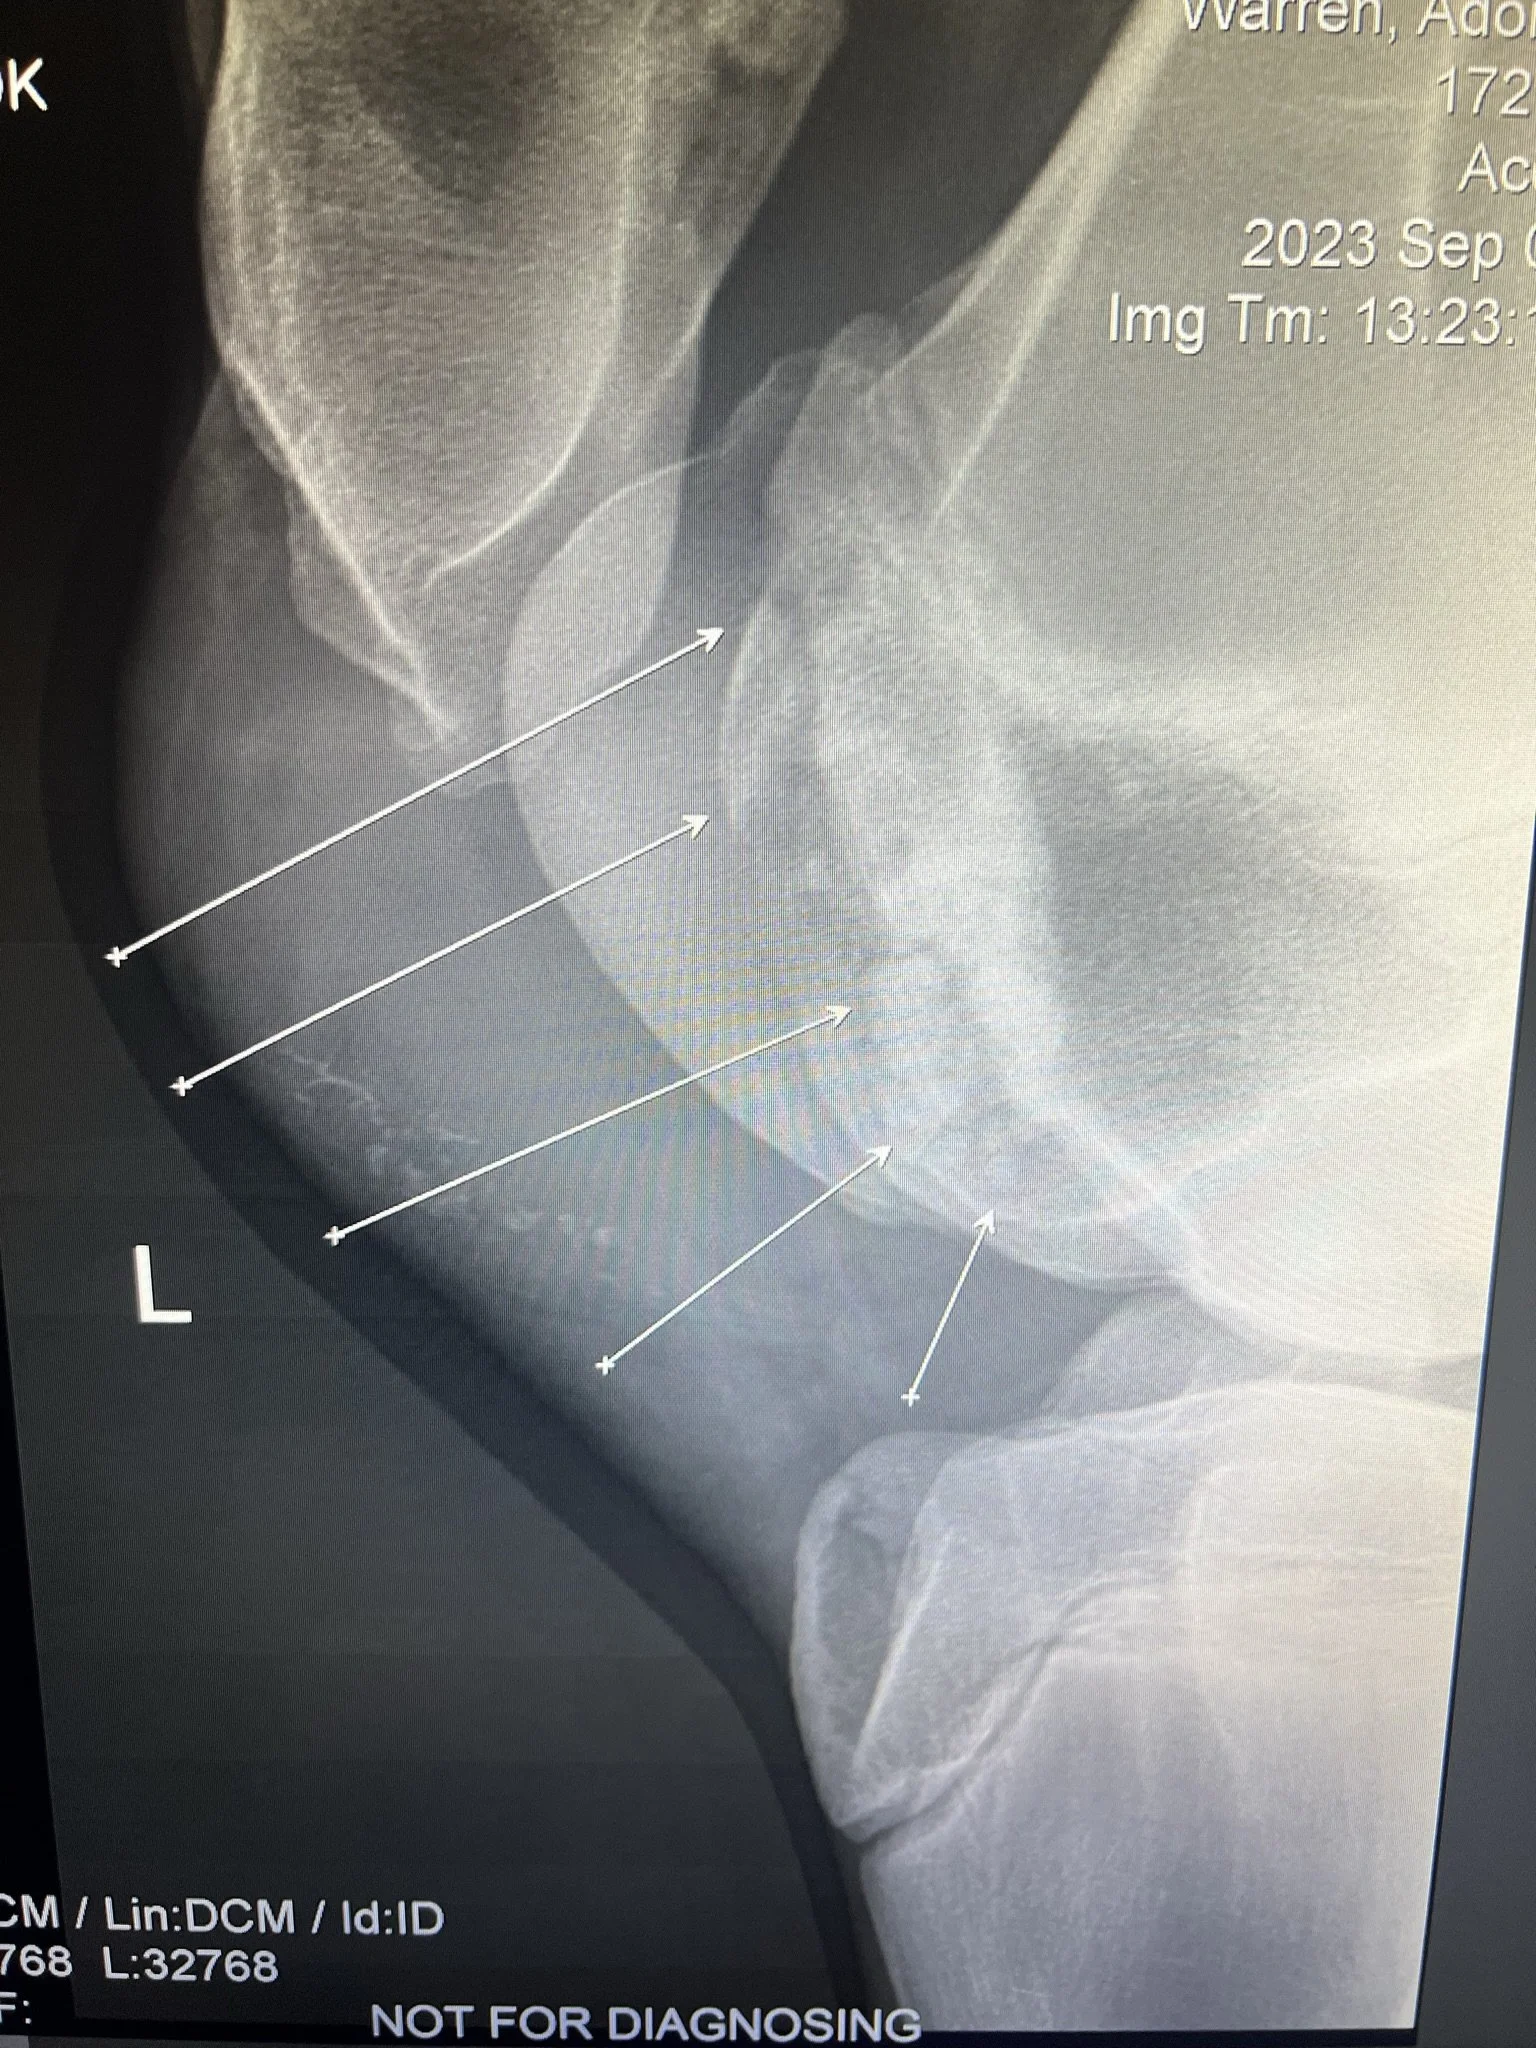

He still needed to be gelded, so while he was under anesthesia, we also did X-rays on his stifles (knees) to see the extend of his condition. He was very sore and slightly lame on his back left leg and had a large swelling/mass on the stifle as well. It turns out he had a whole bunch of bone fragments/cartilage floating around in his stifle (knee). He went up to NH to a specialist for surgery to remove the fragments. Because he had just been gelded, we opted to wait a few weeks for that to heal before we do the stifle surgery. The gelding site and the stifle surgery site would be very close together and have a high risk of any bacteria from that incision to go into the new surgery site. This would cause a bad infection and because they would be working on his bone, it would be a bone infection which is very difficult to heal.

Unfortunately all that proper food and hay with proper vitamins and minerals really made him grow. Normally we would be eastatic! He was finally starting to look like a horse and not a sickly baby moose. In a year, he went from a 15.3hh scrawny thing to a 17.3hh giant! Because of such a rapid growth, he developed more fragments in his stifle. This is nothing we could have avoided, it is just his body growing far faster than his bones.

So a year after his first surgery he went back for his second surgery on the same stifle for the same reason. The staff was happy to have him back and were shocked at how he grew! He had another successful surgery and made a full recovery back to 100%. Although he will probably need some joint injections in that stifle periodically throughout his life, he is 100% sound and loves to run around!